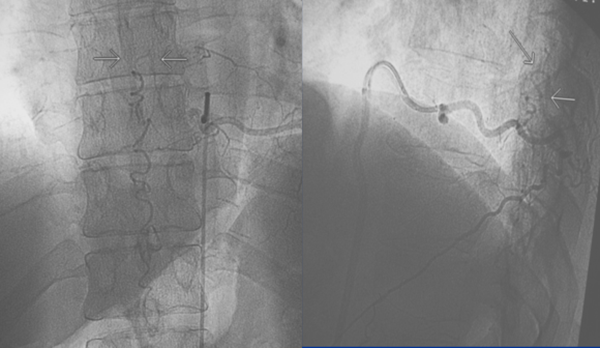

Figura 10: Caso #2. ADM preoperatoria en AP y OAI. La misma arteria radiculomedular D 7 izq. (1) da origen a la arteria de Adamkiewicz (4) y a la FDAVE (2); pie de vena de drenaje (3); horquilla de la arteria de Adamkiewicz (5); arteria espinal anterior (6) y vena espinal posterior (7).

CASO #2. Paciente masculino de 72 años con una historia de 12 meses de parestesias progresivas y ascendentes en ambos miembros inferiores, sin compromiso esfinteriano. Se estudió con RMN (Fig. 9) y una ADM (Fig.10) que muestra una FDAVE en D7 izq. en coincidencia con el origen de la arteria de Adamkiewicz. Fue derivado para microcirugía (Fig. 11). La evolución postoperatoria fue sin déficit neurológico llevando 108 meses libres de enfermedad.